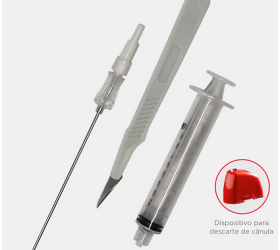

| Kit de Liberação Power Pulse (5 por caixa) | 104834 | 104834-0021 |